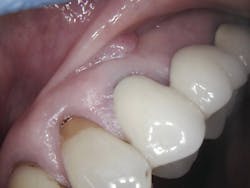

Aiming the laser at the affected area at a 45-degree angle, the first step was to remove the fibroma (figure 3). This was done easily after choosing the appropriate spot size, mist, and power. Following removal, the selections were adjusted for the next step, which was to make an incision in the gingiva. Keep in mind that it was vital to leave approximately 2 mm of keratinized tissue and raise the flap at this time. The laser’s precision allowed for the precise cutting that was needed.

During post-op visits, final results at the three- and eight-month marks and x-rays taken at eight months revealed optimal outcomes that met the clinical objective (figures 8–10).